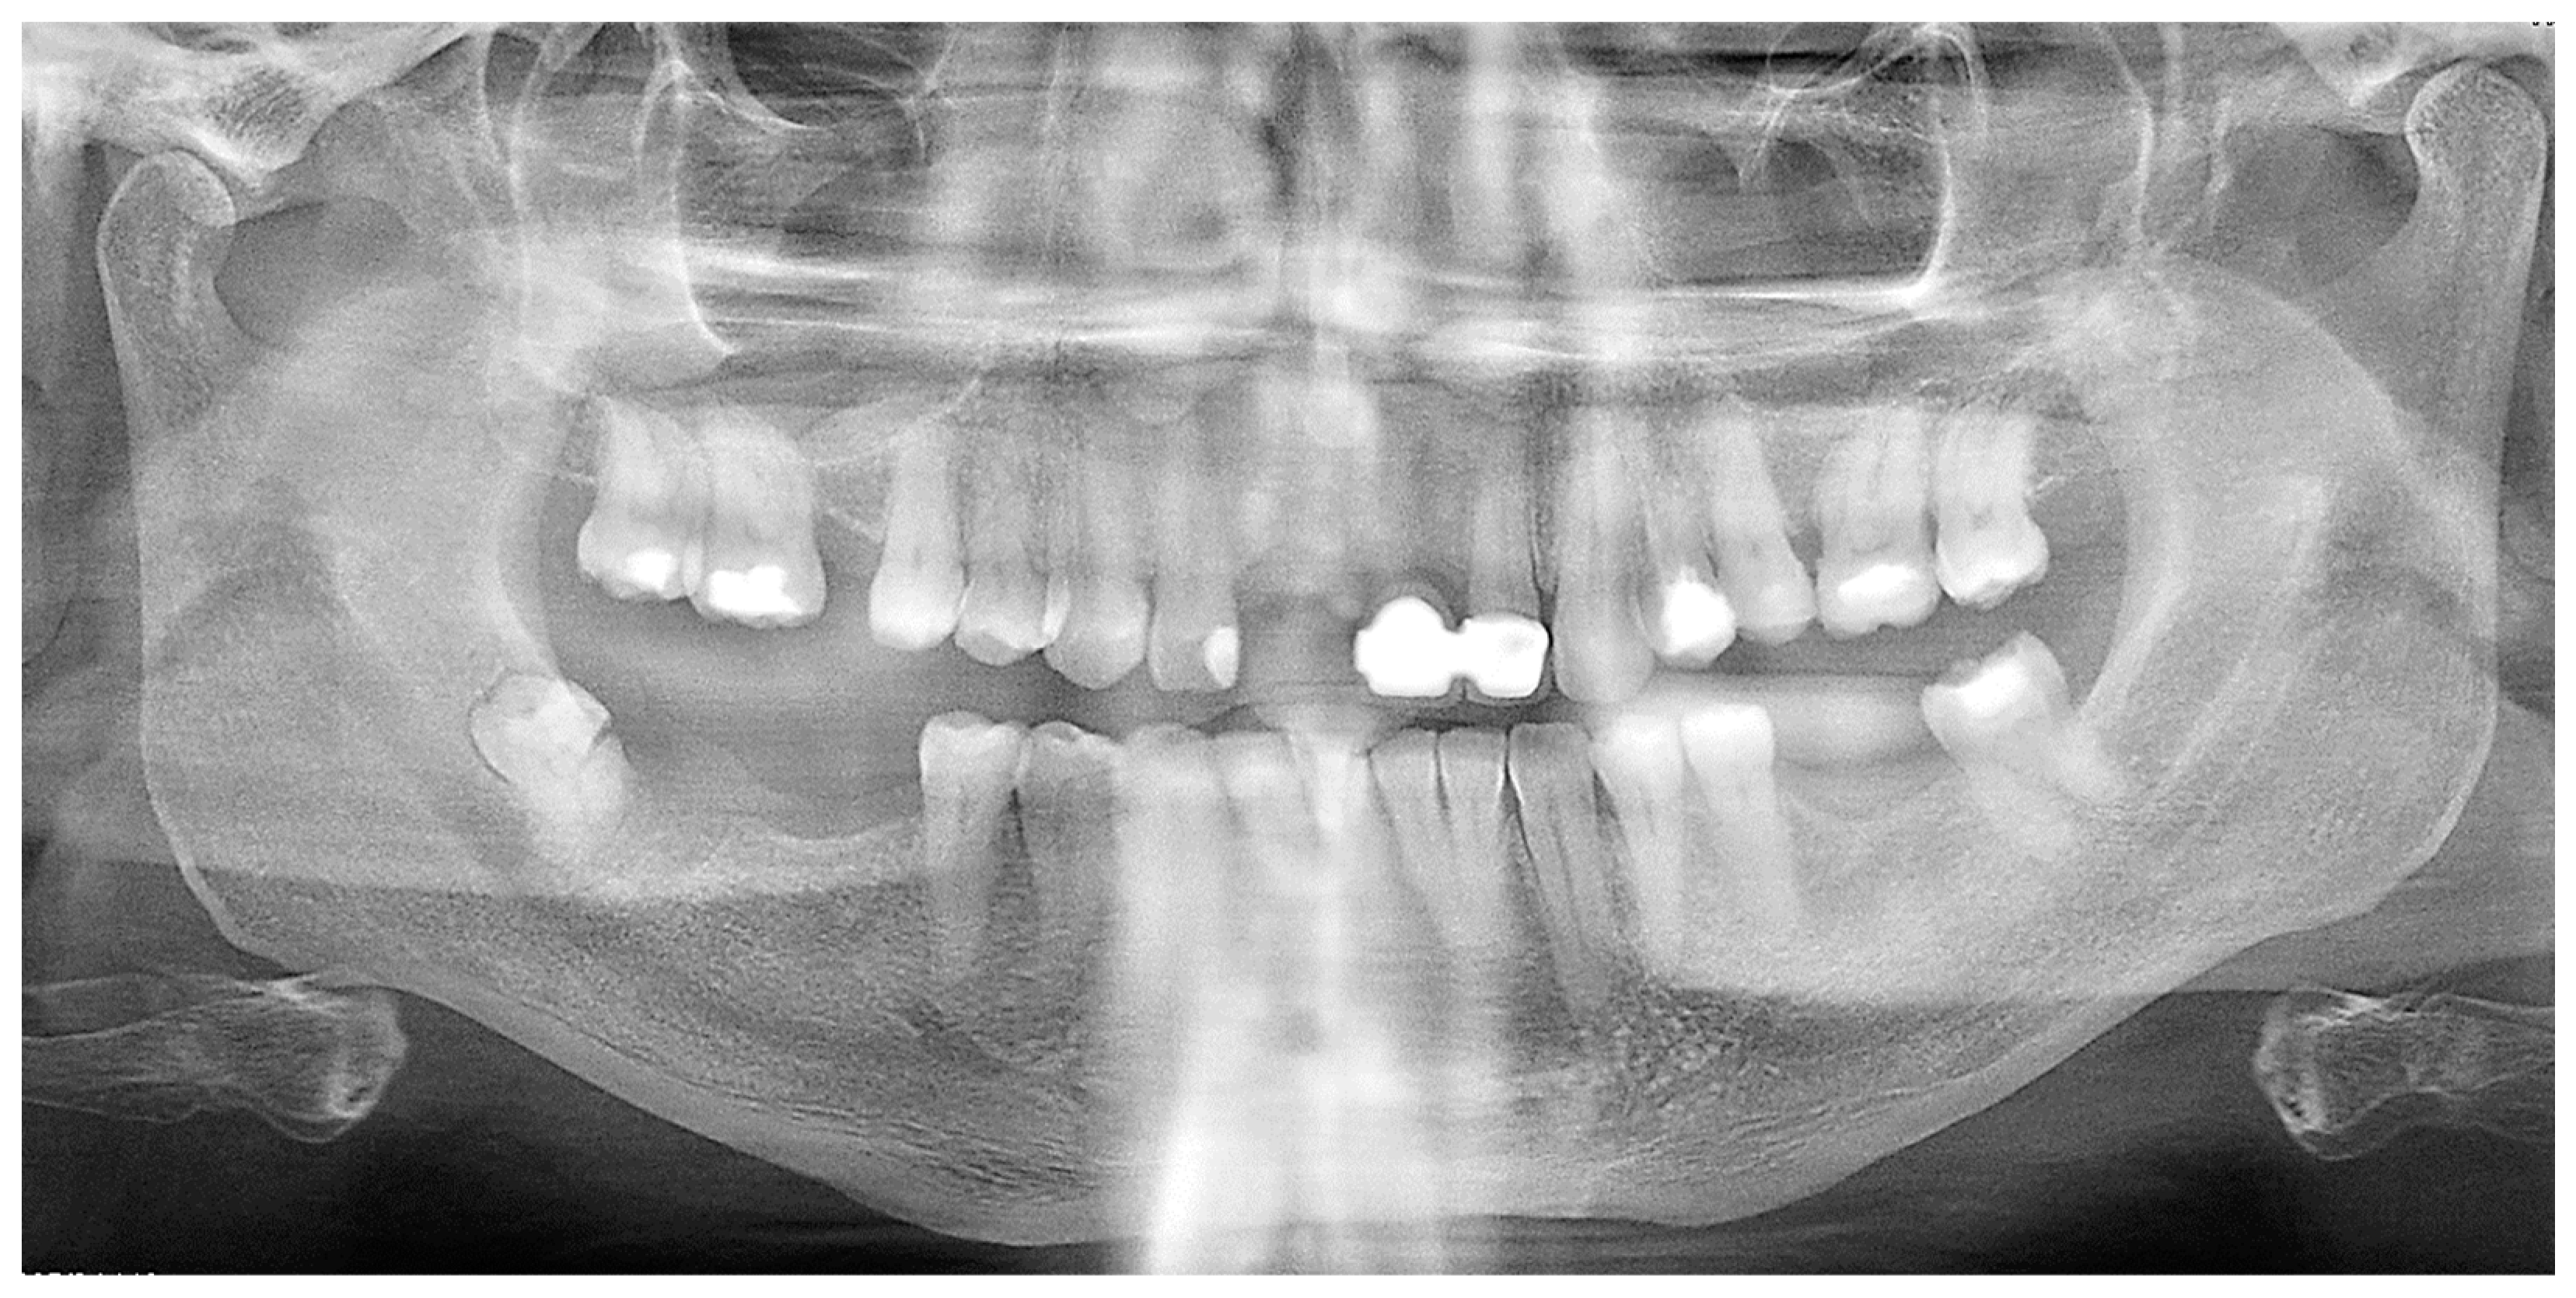

A further orthopantomogram X-ray was performed (Figure 2) and confirmed an impacted fractured wisdom tooth on the right side of the jaw.

Figure 2.

Orthopantomogram (OPT) confirming a semi-impacted fractured wisdom tooth on the right side of the jaw.